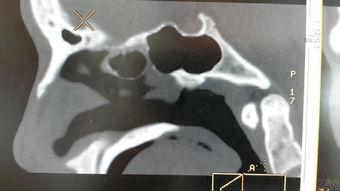

二、鼻骨塌陷的图片,让你大吃一惊!

1. 自然美鼻骨塌陷图片

在网络上,我们可以找到很多自然美鼻骨塌陷的图片。这些图片展示了鼻骨塌陷者在日常生活中真实的样子,让人不禁感叹大自然的神奇。